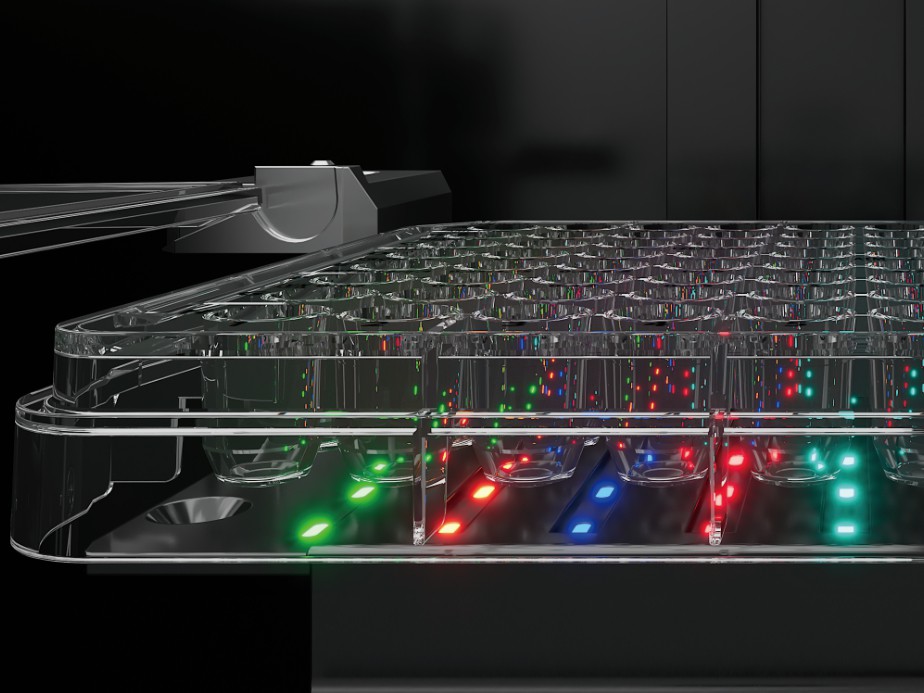

- • Multi-wavelength detection: A five-wavelength detection system is adopted to accurately match the characteristic wavelengths of different biochemical chromogenic reactions to obtain more specific interpretation data and improve the accuracy of results;

- • Dynamic detection: The intelligent dynamic recognition algorithm is used to perform cyclic dynamic (20min) interpretation of the test card, which not only improves the accuracy of the results, but also improves the timeliness of the detection. The results can be produced in 4 to 5 hours at the fastest, which greatly shortens the TAT.